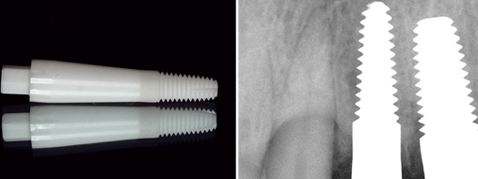

In einer laufenden Studie werden ZrO2- Implantate (Easy-Kon, General Implants, VS-Villingen) auf ihr Osseointegrationsverhalten hin untersucht (Abb. 1). Der verwendete Implantattyp ist ein einteiliges Vollschraubenimplantat mit konischem Gewindeanteil. Die Oberfläche des enossalen Anteils wurde durch ein spezielles Ätzverfahren subtraktiv bearbeitet. Der extraossäre Anteil ist ebenso konisch gestaltet. Somit können divergierende Implantatachsen präparationstechnisch kompensiert werden.

Abb.1: Einteiliges ZrO2-Keramikimplantat Easy-Kon (General Implants, VS-Villingen) mit oberflächen-konditioniertem enossalen Anteil, präparierbarem extraossären Anteil und hexagonalem Kopf für Einbringwerkzeuge. - Abb.2: Regio 12 Kontrollröntgenbild 16 Wochen post implantationem, unmittelbar vor Explantation.